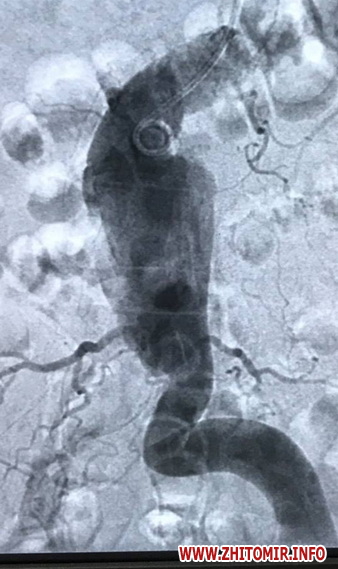

«Вперше в Україні, в Житомирській обласній лікарні, в кардіохірургічному відділенні використано апарат штучного кровообігу з метою швидкої реінфузії крові при резекції розшаровуючої аневризми черевного відділу аорти (диссекція аорти розповсюджувалась на ниркові та здухвинні артерії). Швидкість аутогемотрансфузії 50-500 мл/хв, в умовах повної гепаринізації, об’єм реінфузії 2,5 л. Вага пацієнтки 120 кг. По закінченню операції гемоглобін 123 г/л, інфузія еритроцитів не проводилась. Пацієнтка виписана на десятий день, після оперативного втручання, додому, в задовільному стані. В кардіохірургічному відділенні вже проведено три операції по даній методиці з розшаровуючою аневризмою черевної аорти. Всі пацієнти виписані на амбулаторне лікування», - зазначили в лікарні.